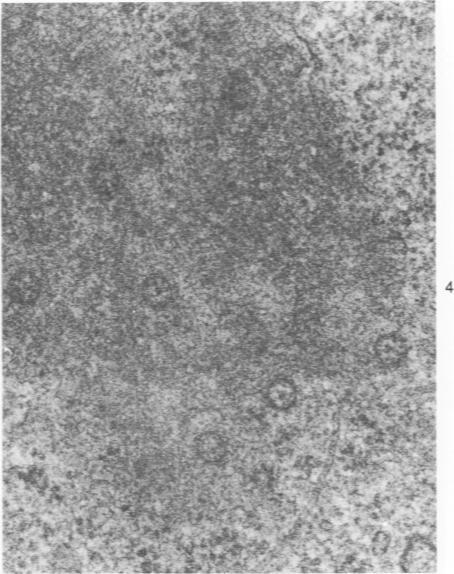

纤维化肺部疾病患者肺泡上皮中的核内包涵体。

Nuclear inclusions in alveolar epithelium of patients with fibrotic lung disorders.

Ultrastructural study of pulmonary biopsy specimens from patients with fibrotic lung disease disclosed the presence of nuclear inclusions in 1% or less of cuboidal alveolar epithelial cells in 9 of 19 patients, including 6 of 12 patients with idiopathic pulmonary fibrosis, 2 of 3 patients with collagen-vascular disease, and 1 of 3 patients with sarcoidosis. Nuclear inclusions were not observed by ultrastructural study in 5 control patients. The inclusions consisted of masses or aggregates of tubules which probably were derived from the inner nuclear membranes. These tubules were smooth-walled, showed branchings and bifurcations, were composed of single trilaminar membranes, usually had a clear content, and ranged from 500 to 1000 A in diameter. They resembled nuclear tubules which occur in other cell types under conditions of rapid growth or specific hormonal stimulation. Statistically significant differences between the groups of patients with and without nuclear inclusions in cuboidal alveolar epithelial cells were not found with respect to smoking history, degree of fibrosis in the lung biopsy specimen, or the degree of pulmonary physiologic impairment. However, the average age of the patients having nuclear inclusions was significantly greater than that of patients not having nuclear inclusions. In addition, the frequency of indentations in the nuclei of cuboidal alveolar epithelial cells was greater in patients with nuclear inclusions than in patients without nuclear inclusions. Highly significant correlations were observed between the presence of nuclear inclusions and the presence of a) anchoring fibrils and hemidesmosomes along the basal surfaces of alveolar epithelial cells and b) multilayering of the alveolar epithelium.

对肺纤维化疾病患者的肺活检标本进行超微结构研究发现,19例患者中有9例(包括12例特发性肺纤维化患者中的6例、3例胶原血管病患者中的2例以及3例结节病患者中的1例),1%或更少的立方肺泡上皮细胞中存在核内包涵体。5例对照患者经超微结构研究未观察到核内包涵体。这些包涵体由可能源自内核膜的小管团块或聚集体组成。这些小管壁光滑,有分支和分叉,由单层三层膜组成,通常内容物清晰,直径在500至1000埃之间。它们类似于在其他细胞类型快速生长或特定激素刺激条件下出现的核小管。在有和没有立方肺泡上皮细胞核内包涵体的患者组之间,在吸烟史、肺活检标本中的纤维化程度或肺生理损害程度方面未发现统计学上的显著差异。然而,有核内包涵体的患者的平均年龄显著高于没有核内包涵体的患者。此外,有核内包涵体的患者立方肺泡上皮细胞核内凹陷的频率高于没有核内包涵体的患者。在核内包涵体的存在与以下情况之间观察到高度显著的相关性:a)沿肺泡上皮细胞基底表面的锚定原纤维和半桥粒;b)肺泡上皮的多层化。